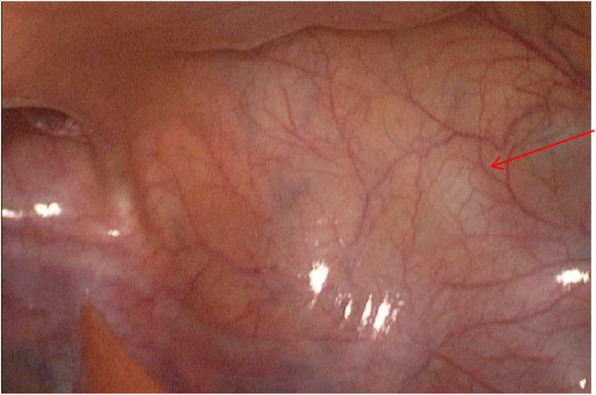

Case presentation: We report the case of an 18-year-old male presenting with urinary pain and was diagnosed with right renal agenesis and a left seminal vesicle cyst following comprehensive imaging. The patient also experienced perineal pain and urgency, without symptoms of frequent urination, dysuria, or hematuria, and no familial history of genitourinary anomalies was documented. He successfully underwent laparoscopic resection of a pelvic mass, with pathological examination confirming a seminal vesicle cyst. Postoperative recovery was uneventful. Whole exome sequencing of blood and tissue samples highlighted myeloma overexpressed gene (MYEOV), B melanoma antigen family member (BAGE), and N-acetylated-alpha-linked acidic dipeptidase 2 (NAALAD2) as potential mutated genes related to Zinner syndrome. Additionally, two predisposing genetic variants were identified.